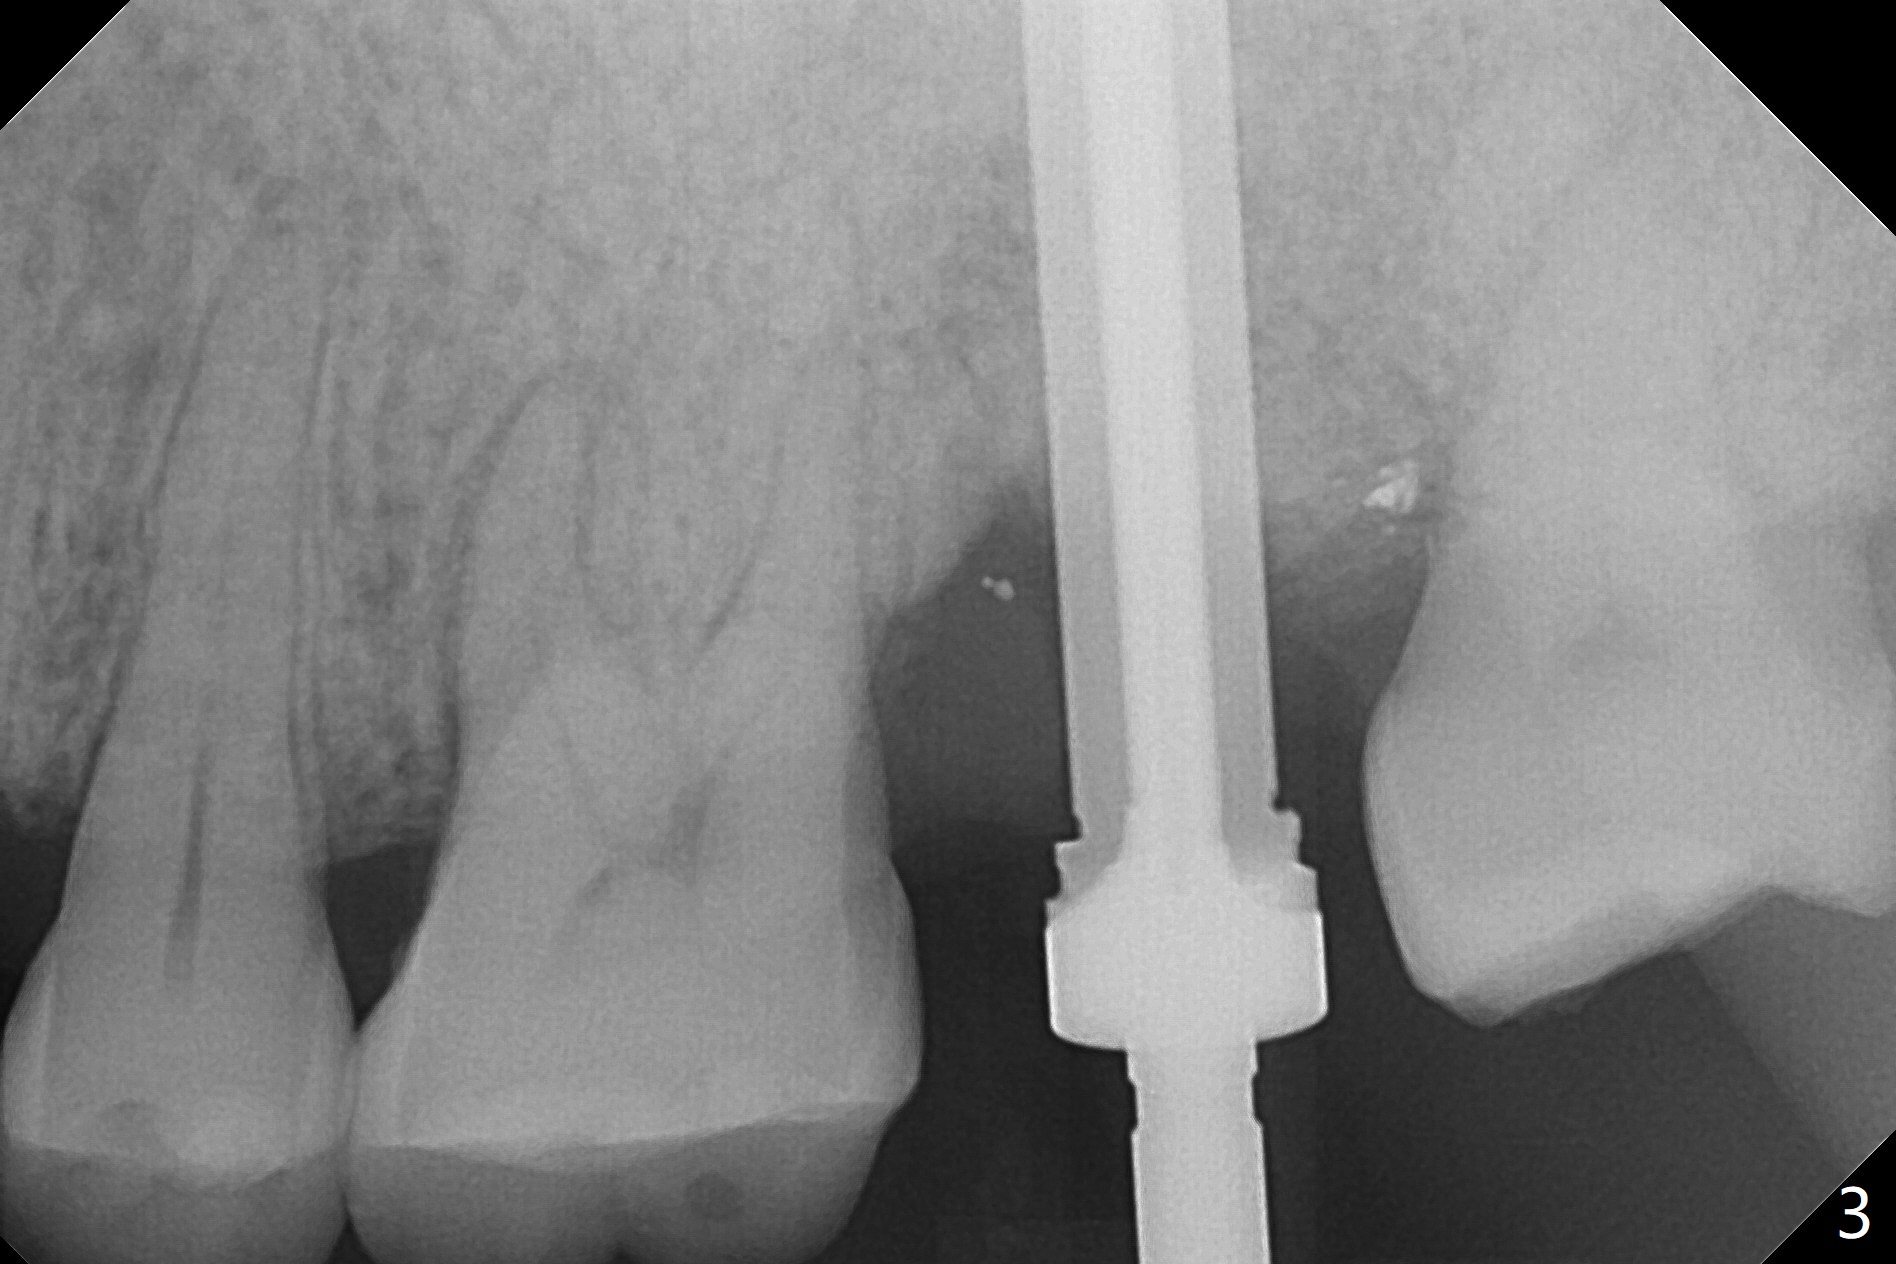

When the patient returns for the tooth #15 extraction and implant, the mesiobuccal residual root has been expelled, while the distobuccal and palatal roots seem to have extruded (Fig.1). The mesial portion of the gingiva (G) is intact and thick. The trajectory of the initial osteotomy is to be changed as shown by red line in Fig.2. The 3.8 mm drill appears to be distal (Fig.3). With mesial bone removal with Lindamann bur, the position of the final implant (5x13 mm) is within normal limit (Fig.4 (50 Ncm)). Because of the thick mesial gingiva (Fig.4 G) and placement of the 5.5x4(2) mm abutment, insertion of mixture of autogenous and Vanilla Graft (*) into the mesial aspect of the implant is difficult (Fig.4 >). Further pushing of the bone graft from the buccal and palatal socket gaps results in more ideal packing (Fig.5 >). If the bone graft were placed first, packing would have been easier. An immediate provisional is fabricated to prevent further mesial shifting of the 3rd molar (Fig.1 arrow). The implant remains stable, while the provisional and abutment are loose 3 months 1 week postop (Fig.6). Impression is taken after abutment cleaning and retightening. Because of the long implant (13 mm), a permanent crown can be cemented early (3 months 20 days postop, Fig.7).